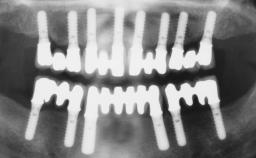

Conventional Loading of Six Implants in the Mandible and Final Restoration with a Full-Arch Metal-Ceramic FDP

A 68-year-old, completely edentulous male patient presented for evaluation and treatment options. He reported excellent general health and was taking no regular medication. He had been edentulous for approximately 12 years, having lost his teeth to periodontal disease and dental caries. The patient’s chief complaint was incompetent function. His secondary concerns included his appearance and the desire for a predictable outcome. He attributed his reduced functional capacity to his lower complete denture, which he described as poor. He was particularly concerned with the denture’s instability and poor fit. In general terms, he was satisfied with the maxillary complete prosthesis. The maxillary prosthesis was characterized by adequate retention, stability, and support, although the fit was considered less than ideal.

# of Implants 6

Type of Implants One-Piece

Defining Characteristics Fully edentulous lower jaw to be rehabilitated with two or more implants

Modality > 4 implants, extending to mental nerve region

Defining Characteristics Fully edentulous lower jaw to be rehabilitated with an implant-borne fixed dental prosthesis